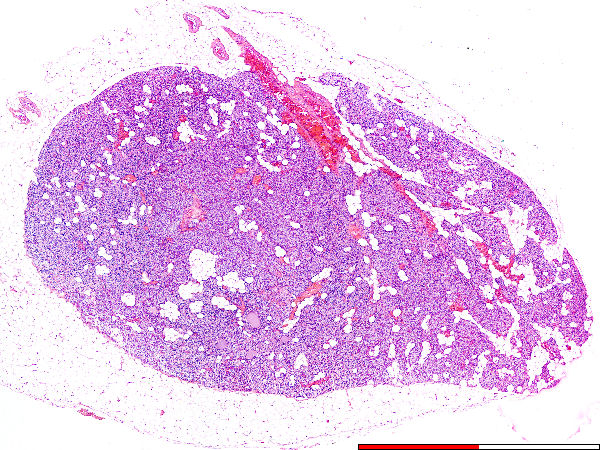

Parathyroid

Kapsel / Capsule

Versamelings van vetselle. / Accumulation of fat cells.

Bloedvate / Blood vessels